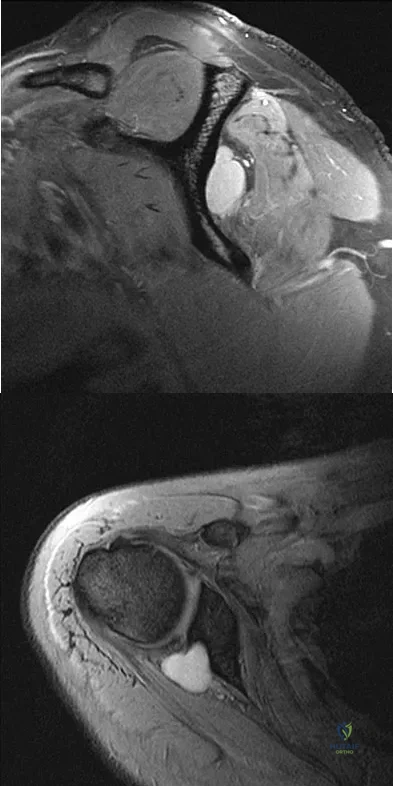

Figures 49a and 49b show MRI scans of the shoulder. What is the most likely diagnosis?

Explanation

A 25-year-old tennis player has shoulder pain and weakness to external rotation. MRI scans are shown in Figures 16a and 16b. What is the most likely cause of his weakness?

Explanation